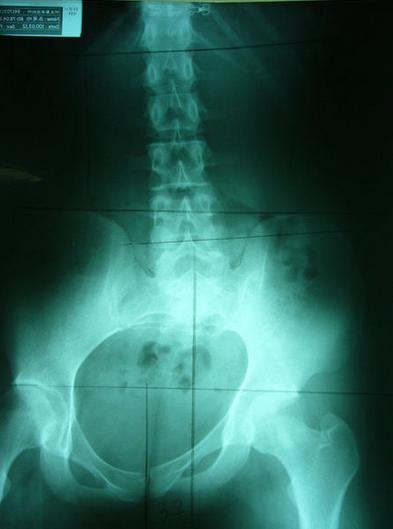

严重不对称案例,伴随腰椎向左倾斜